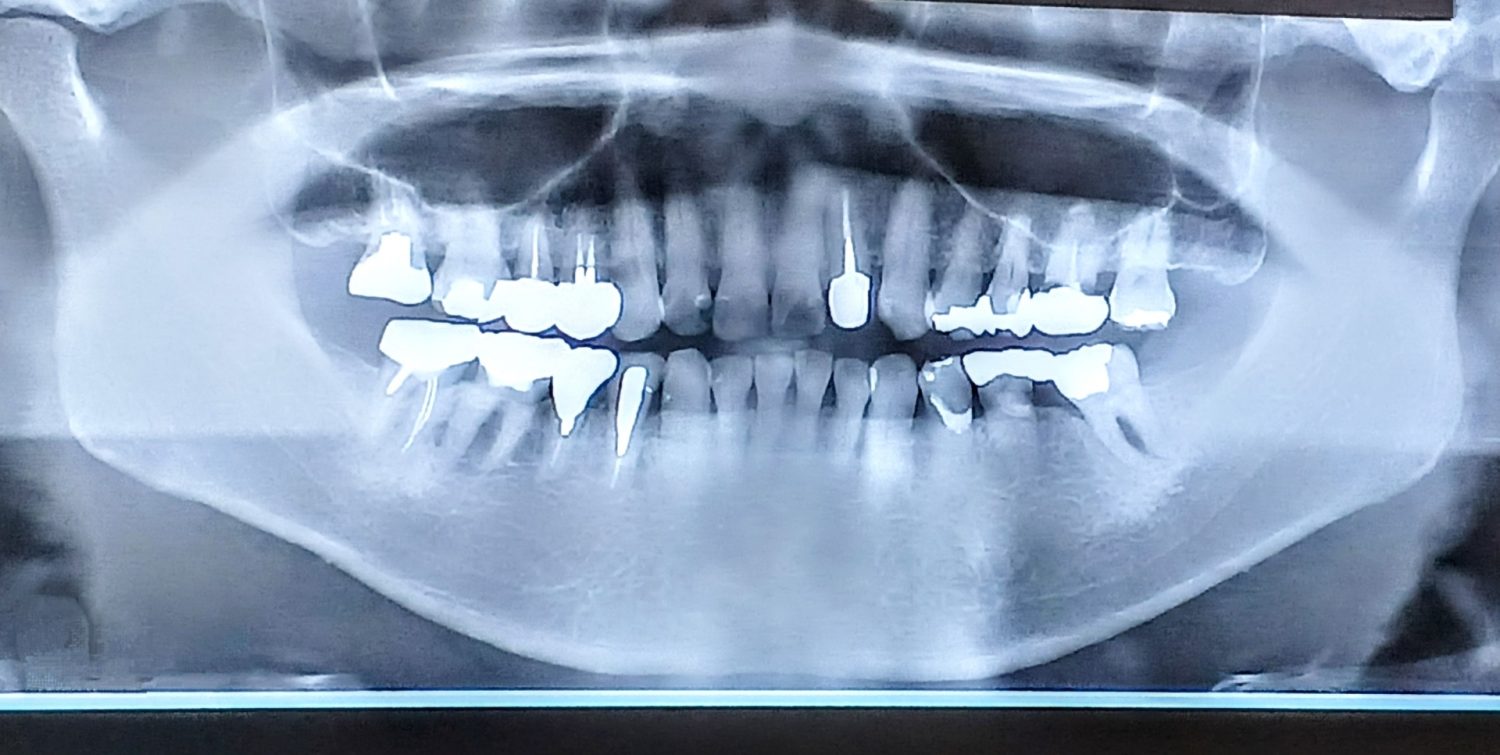

インプラントは顎の骨に人工歯根を固定する治療であるため、十分な骨量と骨質が確保できるかどうかが治療可否や長期的な安定性を左右します。骨が不足している状態で無理にインプラントを埋入すると、噛み合わせの力に耐えきれず、将来的なトラブルにつながるおそれがあります。そのため、骨の状態によってはGBRを行い、土台となる骨環境を整える必要があります。

顎の骨の「厚み」とは、歯茎の内側から外側にかけての幅を指します。例えば、歯を失ってから長期間が経過している場合、噛む刺激が加わらなくなることで骨が徐々に吸収され、インプラントを支えるだけの横幅が足りなくなることがあります。このようなケースでは、インプラントを埋入しようとしても骨からはみ出してしまう、あるいは歯茎側に過度な負担がかかる可能性があります。GBRによって骨の不足部分に骨補填材を填入し、人工膜で覆うことで、新しい骨が再生するスペースを確保します。

骨の高さが不足している状態とは、インプラントを縦方向に十分な長さで固定できない状況を指します。特に上顎の奥歯では、骨の上方に上顎洞と呼ばれる空洞が存在するため、歯を失ったあとに骨吸収が進むと、インプラントを支える高さが不足しやすい傾向があります。高さが不十分なまま短いインプラントを選択する方法もありますが、噛み合わせの力が強くかかる部位では、長期的な安定性を考慮し、GBRによって骨量を回復させてから治療を進める判断がなされることがあります。

なかには、骨の幅と高さの両方が不足しているケースもあります。これは、むし歯や歯周病による抜歯後に長期間放置されていた場合や、炎症が顎の骨にまで及んでいた場合などに見られます。この状態では、インプラントを安定させる条件が大きく損なわれているため、GBRを単独または段階的に行い、骨環境を回復させる必要があります。治療計画は複雑になりやすく、事前の精密検査と十分な説明が重要となります。

この待機期間中は、治療が進んでいないわけではなく、見えない部分で骨の再構築が進んでいる重要な段階です。レントゲンやCT検査を用いて骨の量や質の変化を確認しながら、インプラントを埋入する適切なタイミングを慎重に見極めます。